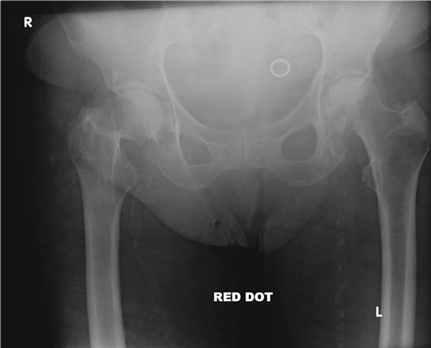

What does this radiograph show and how would you classify this fracture?

There is a displaced intracapsular fracture of the right neck of femur. I would describe this as a Garden IV fracture as there is complete displacement. Clinically the most important classifi cation is simply between displaced and undisplaced fractures.

What would you like to like to know about the patient?

I need to know about any other injuries and the patientโs acute medical status. I would then enquire about medical co-morbidities, residential status and her pre-morbid mobility. Her mental status both acutely and pre-injury are also important.

What is your initial management?

I would manage this patient along the recent British Orthopaedic Association Standards for Trauma (BOAST) guidelines. She requires analgesia, plain radiographs, and admission to an appropriate ward within 4 h. Routine bloods and electrocardiogram (ECG) are performed and the patient rehydrated. I would plan for surgery within 48 h unless a reversible medical condition was present.

How would you manage this patient?

A s mentioned earlier, I would follow the BOAST guidelines. I would discuss treatment with her and propose a total hip replacement (THR). Studies show that patients do better functionally with THR and re-operation rates are lower. I would certainly expect this particular patient to do better with THR. I would use a cemented cup and stem with a 32 mm head via a modifi ed Hardinge approach.

Although relatively uncommon, it is recommended that an orthogeriatrician should be involved in all phases of this patientโs care.

How would you manage this fracture if it occurred in a 42-year-old?

I would aim to conserve the femoral head by reducing the fracture under direct visualization and fi xing internally with three screws.

This patient presented at 10 p.m. Would you operate that night?

I would operate the next morning as evidence suggests that rapid surgery does not aff ect outcome. The most important factor is accurate reduction.